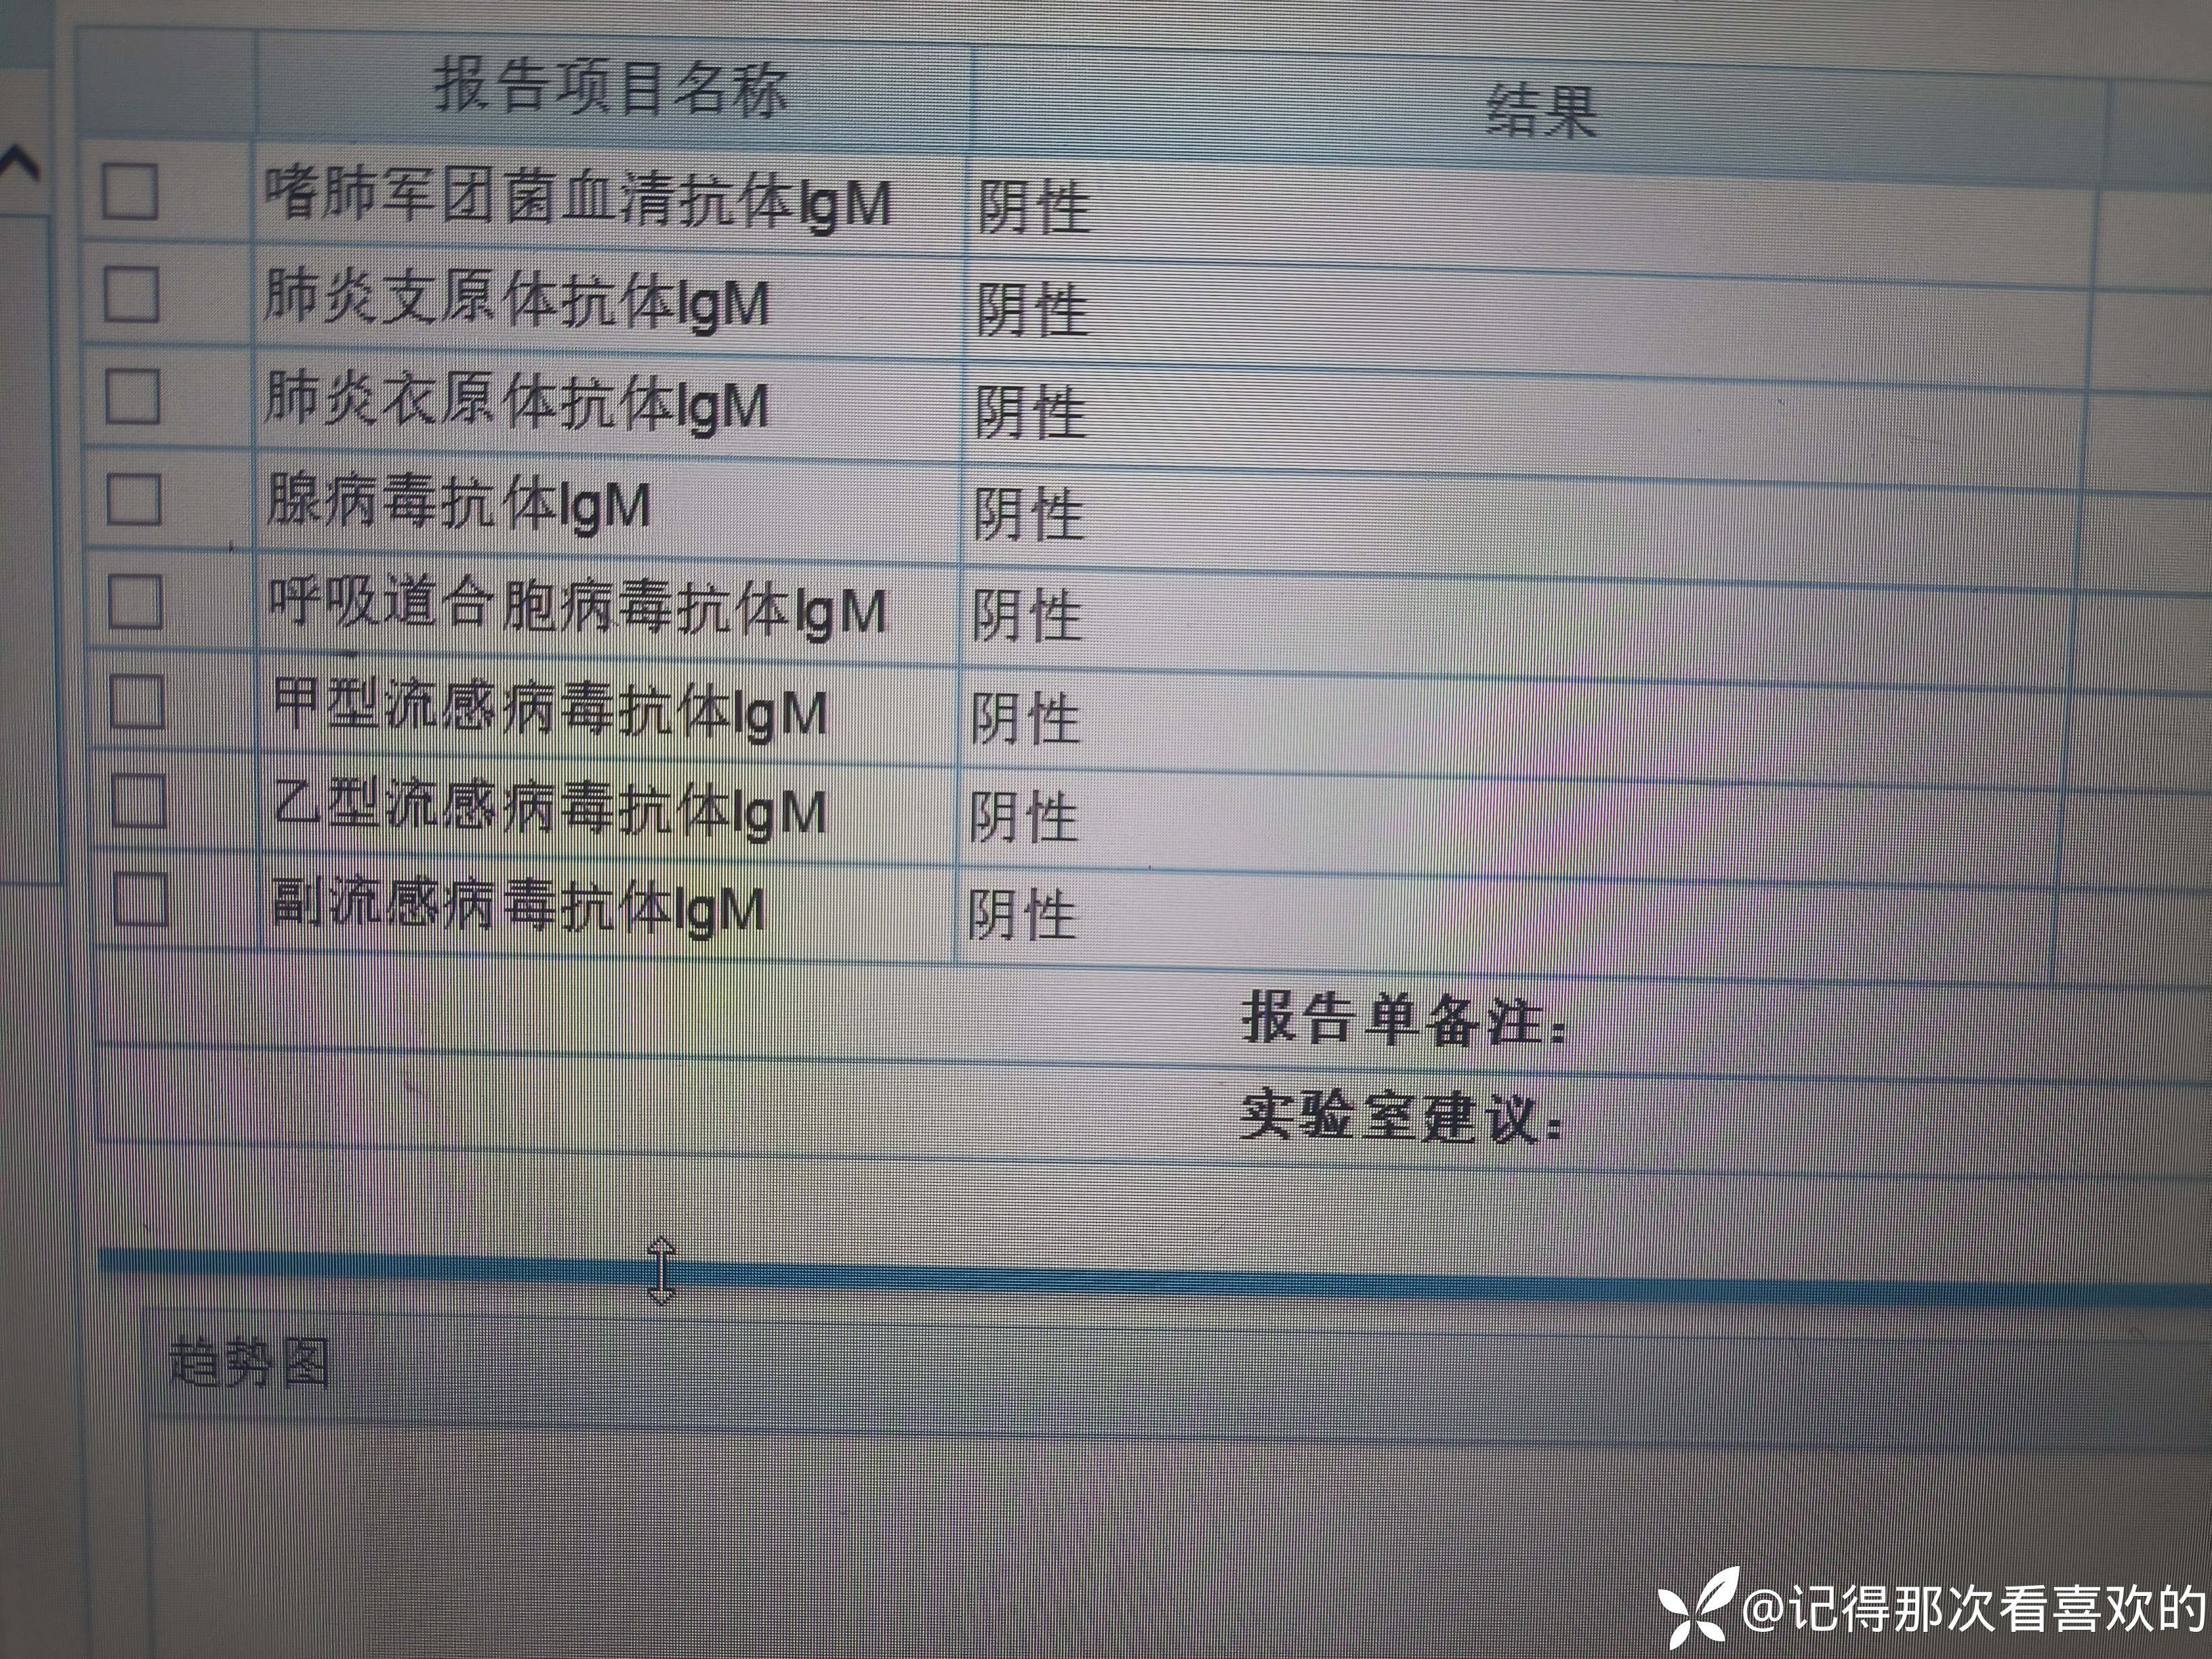

病例特点:患者钟某 男,14岁,以"髋、膝、足肿痛1年余,加重3日。"为主诉入院。现病史:缘于1年前无明显诱因出现左侧髋关节、双足跟、左踝关节、右足第一足趾关节肿胀、疼痛, 疼痛呈持续性,多于阴雨天、活动后症状加重,疼痛未向他处放射、转移,症状严重时行走困难。遂就诊于我科,查"HLA-B27(+)、CRP 70mg/L、骶髂MR:骶髂关节肿胀",诊断为"强直性脊柱炎",先后予皮下注射"司库其尤单抗150mg qw、阿达木单抗40mg q2w",上述症状较前好转,此后不规律用药,于半年前自行停用上述药物,未再规律随诊。3日前再发左膝、双肘关节肿痛,性质同前,程度较前加重,影响行走,伴有发热,体温最高达39℃,自行服用退烧药(具体不详)后体温较前下降,上述关节肿痛无明显改善。现为求进一步治疗,就诊我院,门诊拟"强直性脊柱炎"收住入院。体格检查:T36.6℃ P138次/分 R50次/分BP/120/68mmHg 专科情况:生命征平稳,神志清楚,双肺呼吸音清,未闻及干湿啰音,心律齐,各瓣膜听诊区未闻及杂音,全腹软,无压痛及反跳痛,未触及包块,双肘、左膝关节肿胀、压痛、触之皮温高。双下肢无浮肿,病理征未引出。

诊疗计划:1.入院予二级护理,监测血压、脉搏、呼吸。2.入院完善三大常规、凝血、生化、骶髂MR、彩超、CT、心电图等相关检查评估病情。3.治疗上暂予抗炎镇痛,辅以护胃治疗,待相关检查结果回报后进一步治疗,本次就诊拟行生物制剂治疗,予完善骨保护药物,传染病相关检查排除禁忌症,患者本次发病伴有发热达39℃,追问病史患者诉偶有干咳不适,目前已改善,予完善呼吸道病原学检查明确病情。4.患者Padua评分1分,属于发生VTE低危风险,实行VTE基本预防,动态评估Padua评分。5.已将目前病情及现有临床诊断以及存在疾病复杂性、个体的差异性、对治疗的反应不同、鉴于目前医学技术水平有限,和下一步相关诊疗详细充分告知患者家属,取得家属的理解并同意配合下一步诊疗及检查。6.NRS-2002评分3分,目前患者营养状态尚可,进食情况尚可,根据病情变化动态评估。